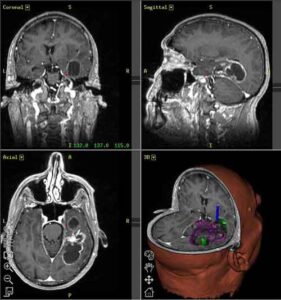

Un gruppo di ricercatori di Sapienza e dell Istituto Pasteur di Roma ha presentato i risultati di una ricerca che...